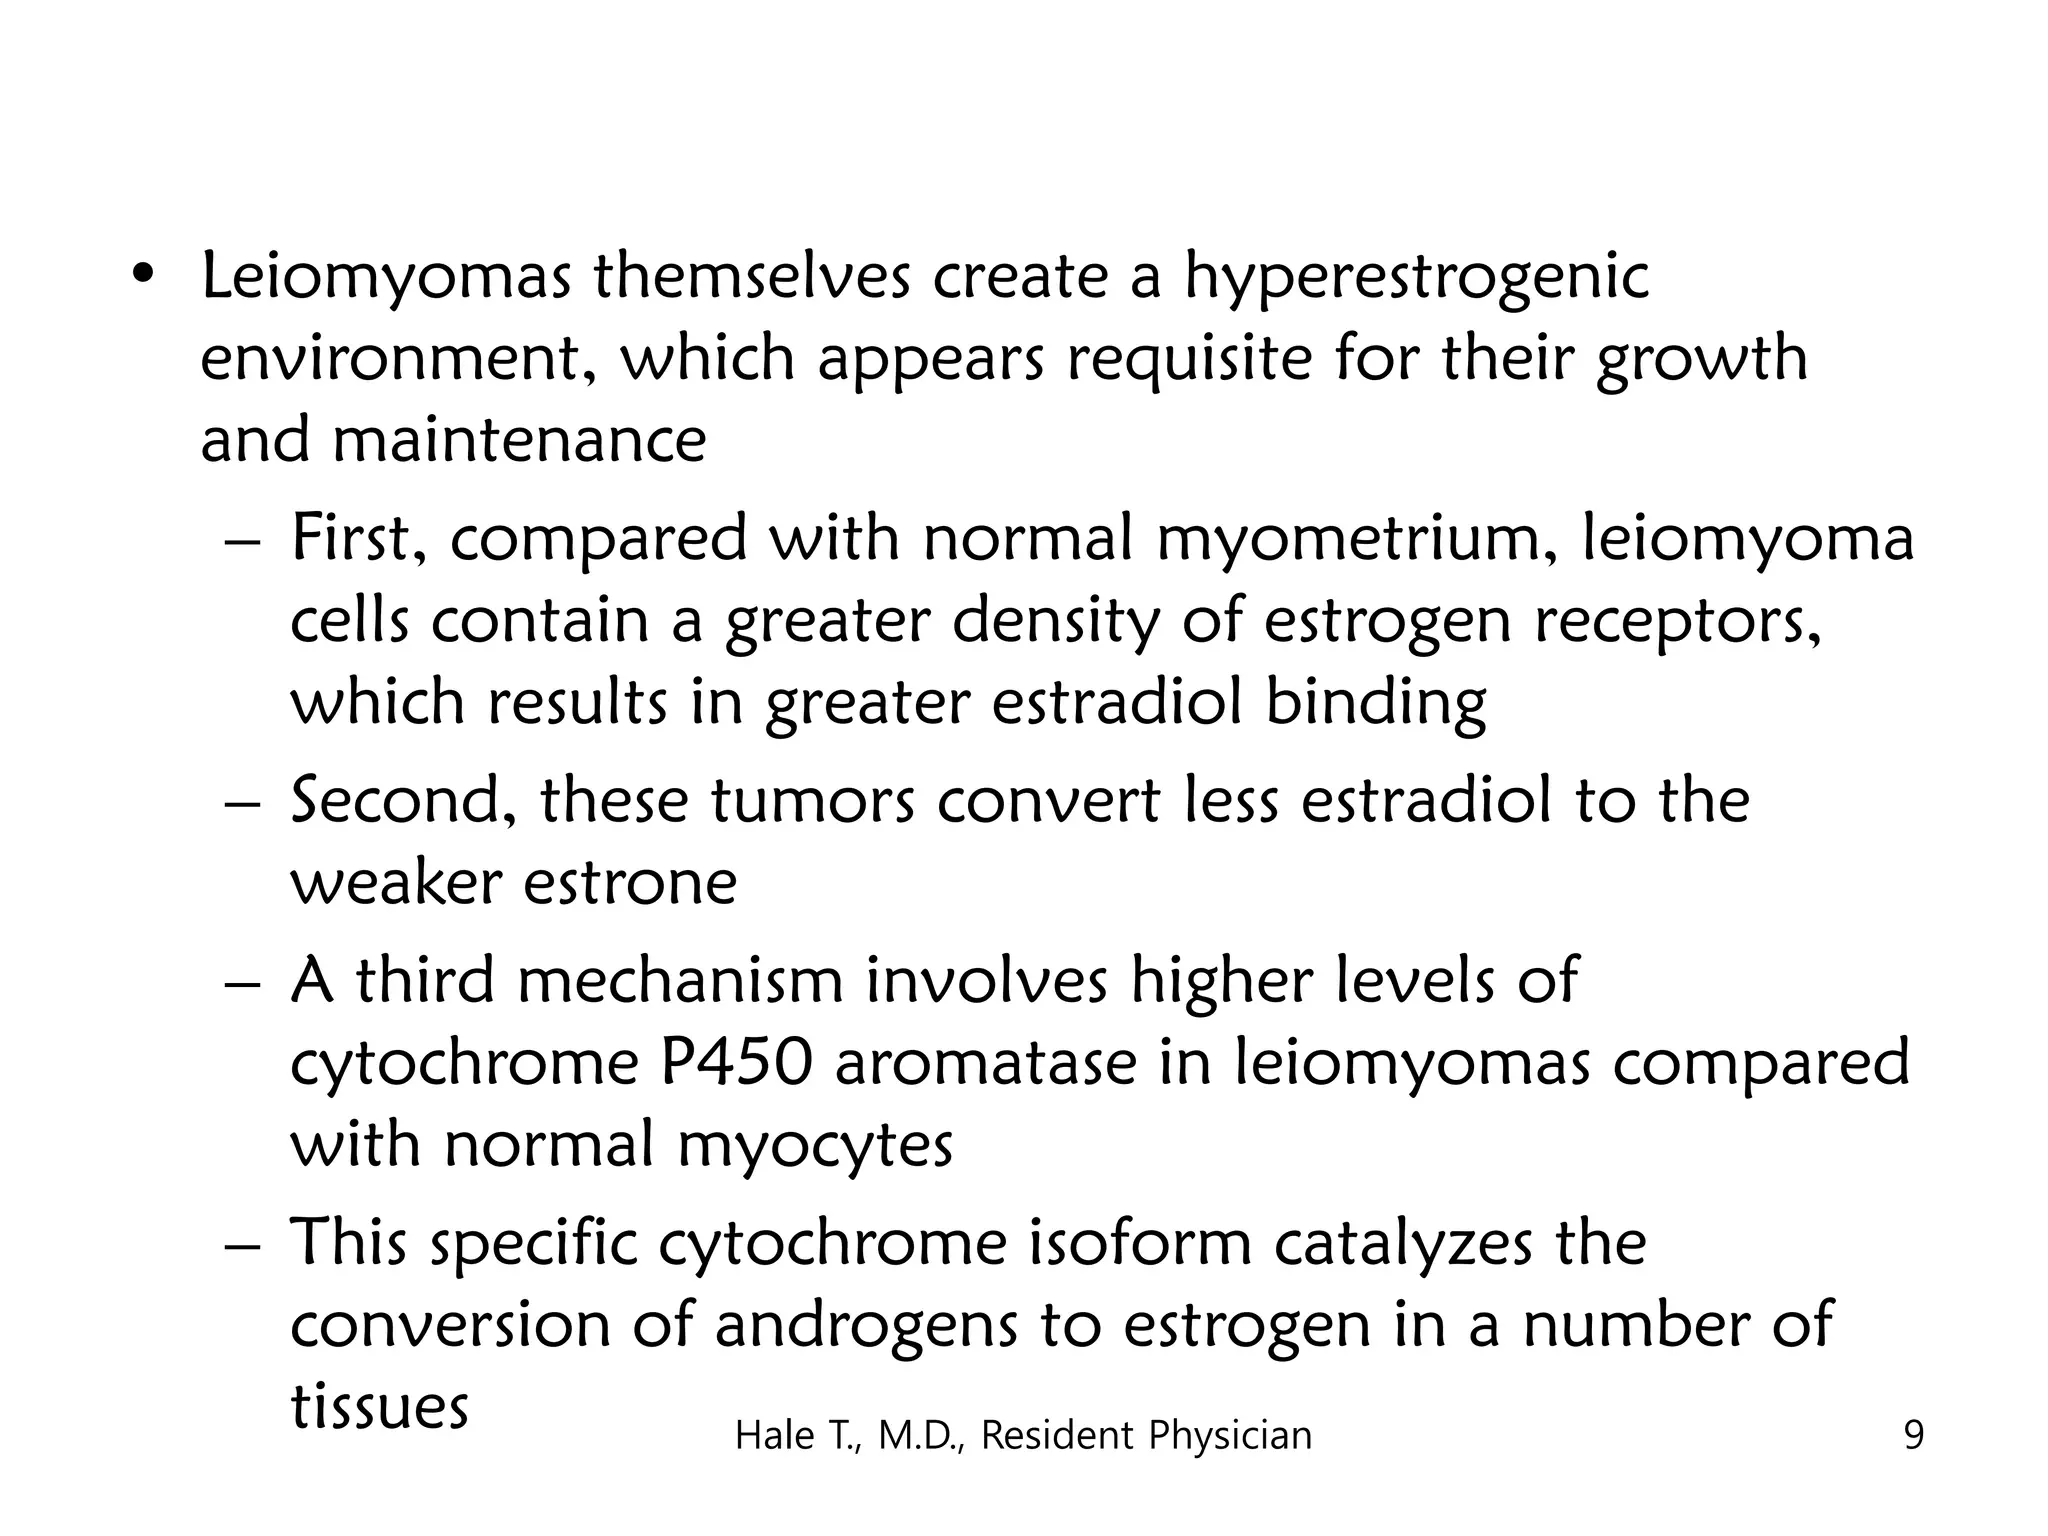

This document discusses myomas (uterine fibroids). It notes that myomas are benign smooth muscle tumors that originate in the uterus and are sensitive to estrogen and progesterone. Symptoms can include bleeding, pain, pressure, and infertility. Diagnosis is usually made through imaging like ultrasound or MRI. Treatment options include observation, drug therapy, uterine artery embolization, or surgical removal of the fibroids. The document also discusses complications that can arise if fibroids are present during pregnancy, such as pain, bleeding, preterm birth, and pregnancy loss.